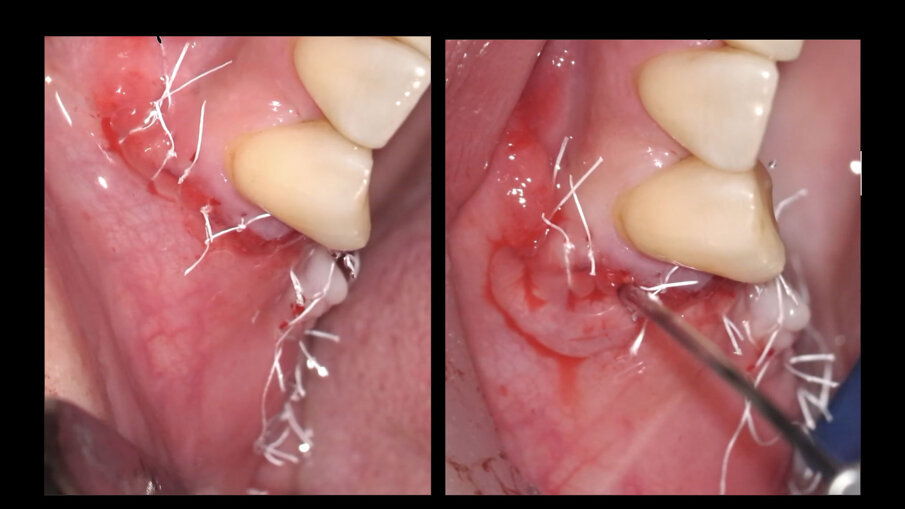

La procedura termina con il rilascio del lembo vestibolare, una seconda applicazione di Regenfast sulla superficie della membrana stabilizzata, la chiusura dei lembi per prima intenzione mediante una combinazione di punti a materassaio interno e punti staccati, ed una terza applicazione di Regenfast al di sopra della linea di chiusura (Figg. 5, 6). Dimessa la paziente in stato vigile e orientato, con coagulo competente, si rimuove la sutura a distanza di 14 giorni, riscontrando un decorso post-chirurgico nella norma (Fig. 7).

Fig. 5 - Applicazione stratificata di Regenfast durante la tecnica GBR.

Fig. 6 - Chiusura del lembo ed applicazione finale di Regenfast sulla linea di sutura.

Fig. 7 - Guarigione a 14 giorni.